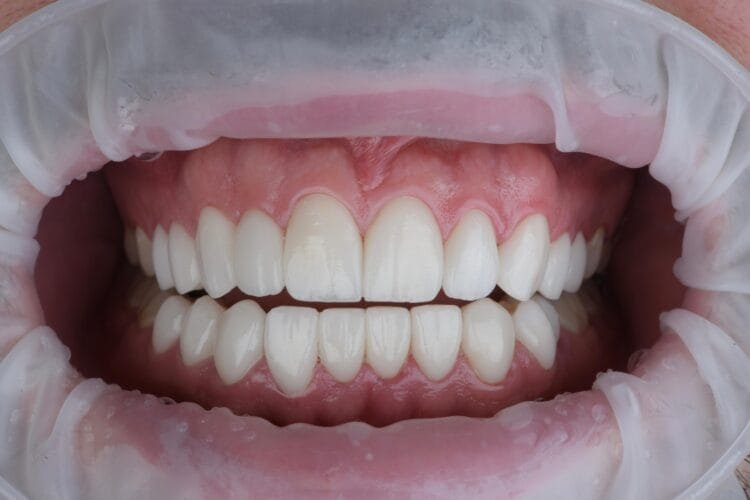

Ich habe meine Doktorarbeit an der Gazi Universität, Abteilung für Prothetik, zum Thema "Der Einfluss verschiedener Zementfarben auf die Farbe bei vollkeramischen Restaurationen" geschrieben. Ich habe mein Fachwissen durch akademische und wissenschaftliche Studien vertieft.

Mit meinem Promotionsverfahren an der Gazi Universität biete ich Dienstleistungen mit einem wissenschaftlichen Ansatz in der ästhetischen und prothetischen Zahnbehandlung an. Jeder Behandlungsplan wird auf der Grundlage aktueller wissenschaftlicher Erkenntnisse gestaltet.

Ich plane speziell für die Bedürfnisse jedes einzelnen Patienten und arbeite akribisch bis ins kleinste Detail, um Ihnen ein natürliches und ästhetisches Lächeln zu ermöglichen.